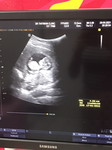

กำลังตั้งครรภ์